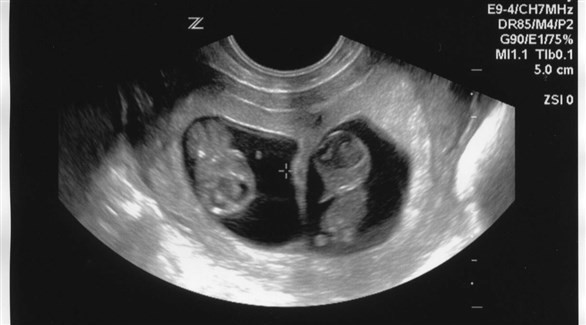

الحمل بتوأم أو أكثر

يزيد خطر تسمم الحمل بشكل ملحوظ عند الحمل بتوأم أو أكثر، نتيجة لزيادة الحمل الهرموني والحجمي على الجسم.